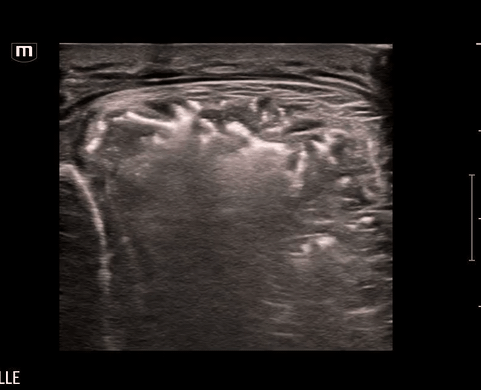

Using the linear probe for better visualization of superficial structure, let’s take a look at what we saw on the left lower leg:

What do we see?? Air and “dirty shadowing” in the soft tissue concerning for necrotizing fasciitis in this clinical context.

We can identify necrotizing fasciitis on US by using the acronym “STAFF”

• S – Subcutaneous thickening: diffuse thickening and distortment of soft tissue layers seen

• T – Thickened fascia:  chunky fascia not a thin bright white line

• A – Air: posterior dirty acoustic shadowing, corresponding to gas in the soft tissue

• F – Fascial fluid: Anechoic fluid collections (<2mm)

• Necrotizing intramuscular and soft tissue infection with abscess formation within the anterior tibialis muscle, extending to the mid-femoral diaphysis and posterior distal thigh